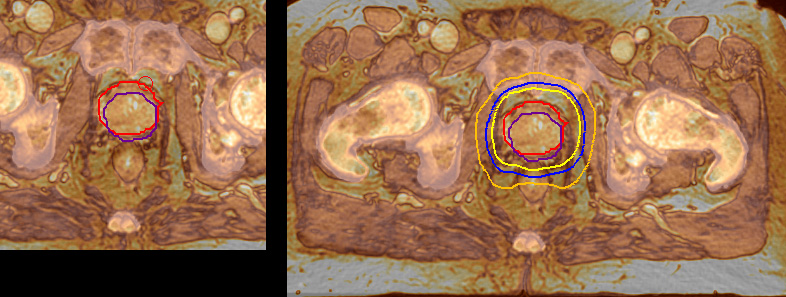

“When a patient registers, first CT simulation and MR simulation are done, followed by CT-MR registration on Pinnacle3. Then the target and normal organ delineation is performed on MR images. Meanwhile we create a reference CT image for online treatment and localization correction. During the treatment phase we can perform additional MRI scans to visualize the anatomy changes and create an adaptive plan. This plan basically adapts the treatment plan to the changes.” “Along with its great benefits, MR has introduced some new challenges,” Dr. Stevens says. “Radiation therapy teams generally have no experience with MR. The Philips training helped us to implement fully the things we can do with the Ingenia MR-RT system. So the training, as well as having a good MR physicist, is critical.”

“The biggest problem for CT-based planning, especially in prostate, is you can’t see the cancer very well,” says Dr. Stevens. “On CT it can be quite challenging to see the edge of the prostate especially at the apex. When the edge of the prostate can’t be delineated well on CT, radiation oncologists will increase their margins a little bit so they don’t miss it, but that can also increase toxicity.” “Using MR, the prostate is well delineated. We quickly see the edges of cancerous tumors like in prostate cancer, and as normal structures can be defined, we can optimize the treatment plan to protect these organs and their normal function. This can potentially improve the outcome. And it improves workflow as well. We can contour more quickly, confident that the tumor is going to be in the field.” “The Ingenia 3.0T MR scanner provides high resolution allowing us to make scans fast for the patients. It also gives the potential to include methods like MR spectroscopy and diffusion weighted Imaging, which we’re in the process of doing right now,” Dr. Stevens adds.

“There are some general challenges in RT imaging – even with CT – such as imaging geometry and positioning accuracy. Positioning is extremely important in RT, because we need reproducibility between imaging and treatment position. We also need accurate geometry so we can be sure our treatment plan is properly delivered during the treatment,” says Dr Yan. “The Ingenia MR-RT configuration includes an external laser positioning system for patient alignment and a flat tabletop for imaging the patient in treatment position. Ingenia MR-RT also came with a special QA package for regular monitoring of precision. Our Ingenia 3.0T scanner achieves good geometric accuracy – within a millimeter for most patients – and the phantom measurement is even better,” he adds. “Ingenia’s wide 70 cm bore is valuable to easily accommodate immobilization devices needed in RT,” says Dr. Stevens. “With a small bore MR scanner you can’t get the RT immobilization devices into the scanner properly; the large bore makes it easy to image patients in their immobilization device.”